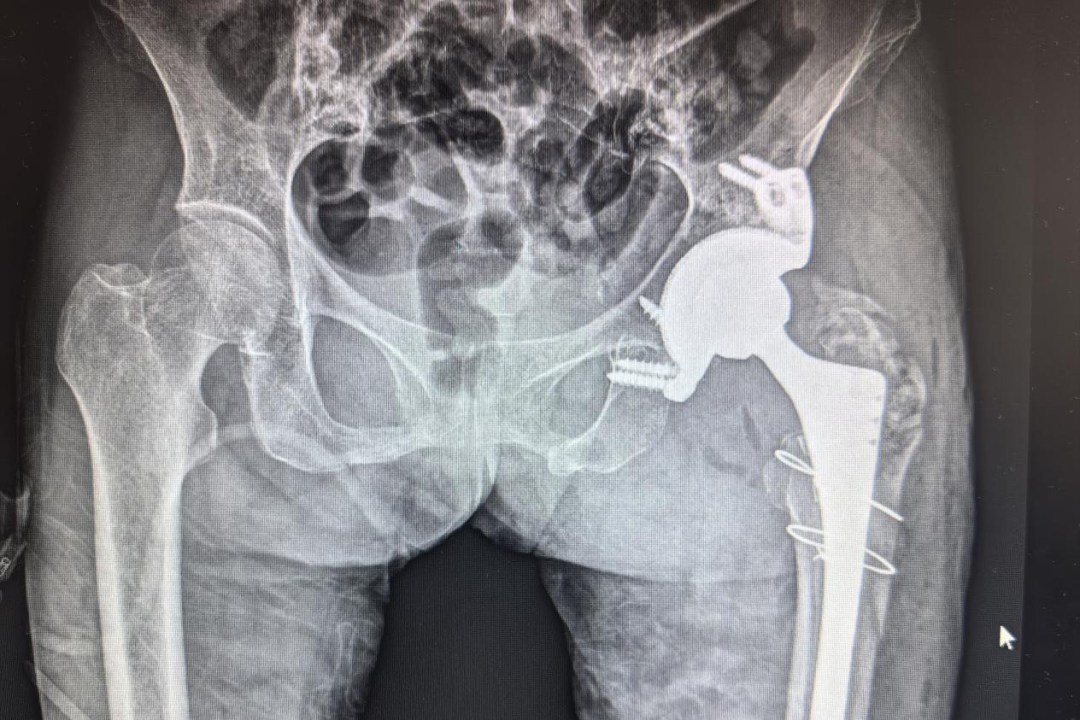

图片

手术后X线复查

手术前三维CT

近日,廉江市人民医院关节外科成功完成一例高难度3D打印个性化髋臼假体行全髋关节翻修手术,为一名髋关节置换术后假体松动,行走困难的患者李某重建髋关节功能。术后1周患者下床活动,并顺利出院。这一手术的成功实施,标志着廉江市人民医院在复杂髋关节翻修手术领域达到粤西地区县级医院领先水平,为骨科精准治疗树立了新标杆。

医疗团队经过详细术前讨论,三维CT髋臼重建后考虑患者髋臼缺损较大,常规假体无法满足需求,面对如此复杂的病情,最终决定采用3D打印个性化髋臼假体技术为患者定制专属假体,确保假体的稳定性和力学性能。最终关节外科岑怡彪主任团队为患者完成了左侧髋关节清理+定制髋臼假体重建+股骨柄翻修+股骨上段骨折切开复位内固定+异体骨植骨术,术后X线显示,假体位置精准,与髋臼缺损区契合。术后第13天患者出院,步态行走基本正常。